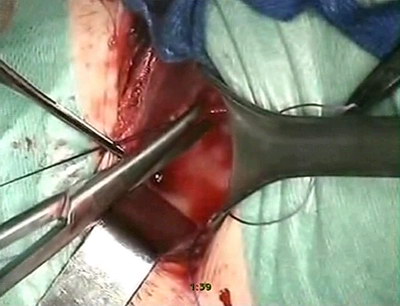

Выполнено оперативное вмешательство:

Трансвезикальный уретероцистоанастомоз

по Коэну

Протокол и ход операции:

Под эндотрахеальным наркозом произведен разрез по Пфаненштилю,

послойно с поперечным рассечением апоневроза, тупо разведена

прямая мышца живота, выделена и взята на держалки передняя

стенка мочевого пузыря, последняя рассечена поперечно на

протяжении 5-6 см. Устья мочеточников визуализированы в

типичных местах. Поочередно с двух сторон выполнено выделение

устьев мочеточников, мобилизация нижних третей мочеточников

на протяжении 3-4 см. Мочеточники расширены до 15мм в диаметре,

в области интрамуральных отделов определяются их сужения.

Мочеточники перекрёстно уложены в подслизистый тоннель между

устьями в области треугольника Льето. Выполнена резекция

мочеточников на протяжении 2 см и анастомоз со слизистой

мочевого пузыря викрилом 4/0 выше устьев мочеточников. Слизистая

мочевого пузыря ушита викрилом 4/0. Мочеточники интубированы.

Установлена цистостома. Стенка мочевого пузыря ушита двойным

непрерывным викриловым швом, цистостома фиксирована к мочевому

пузырю, дренажи-интубаторы выведены через контраппертуры

на переднюю брюшную стенку, фиксированы. В рану установлен

резиновый дренаж. Гемостаз. Сухо. Кровопотеря - 100мл. Рана

ушита послойно, косметический шов на кожу. Обработка йодопироном,

асептическая наклейка.

Время операции: 1час 25 минут